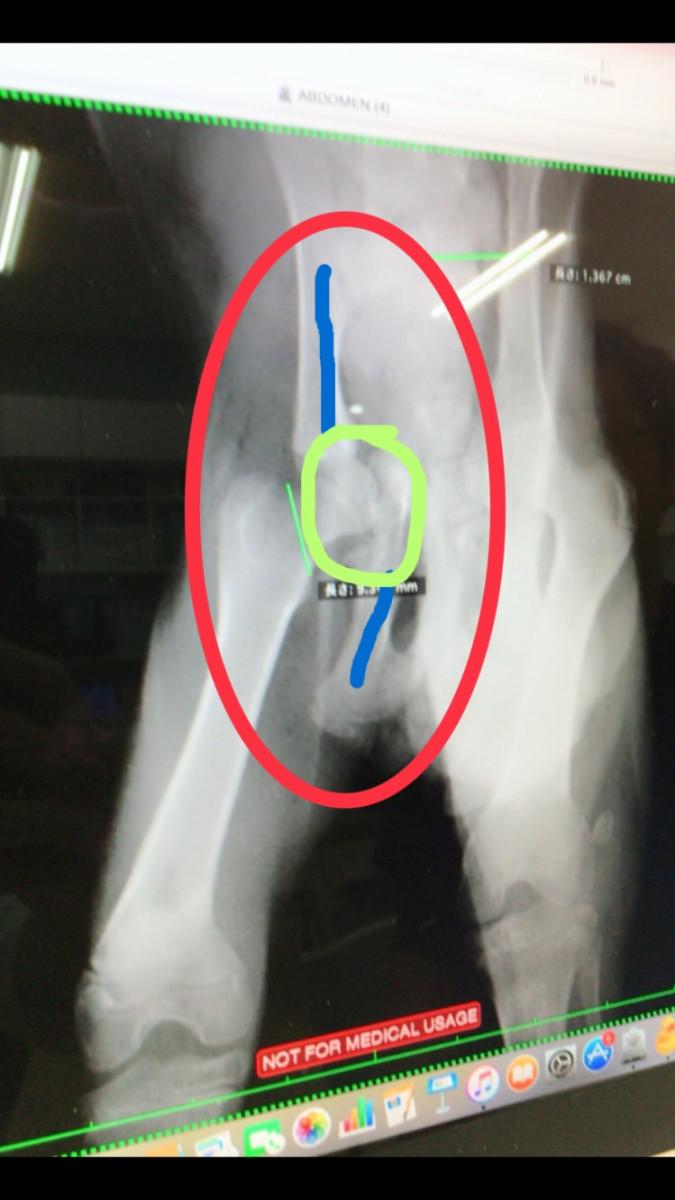

1枚目が原画です。

2枚目は私がちょっと加工してます。

2枚目の画像でお話しすると、

本来青い2本の骨はくっついていないといけない骨だそう。

けど、そこが折れて緑の丸部分の大腿骨が食い込んでる状態。

なので緑の線から食い込んでるとこは切除するという手術でした。